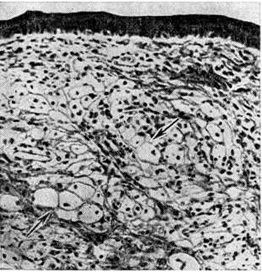

Ксантома (xanthoma; греческий хапthos золотисто-жёлтый + -oma; синонимы: сальный моллюск, липоматозная фиброма) — очаговое отложение в коже и некоторых тканях триглицеридов и холестерина, вызванное нарушениями жирового обмена. Термин «ксантома» введён в 1864 год Смитом (W. F. Smith). Морфологически основой Ксантома являются так называемый ксантомные клетки (рис.) — одно или многоядерные фагоциты с пенистой цитоплазмой, содержащей двоякопреломляющие жировые включения; в дерме может быть лимфогистиоцитарная инфильтрация, встречаются гигантские клетки инородных тел, прогрессирует фиброз.